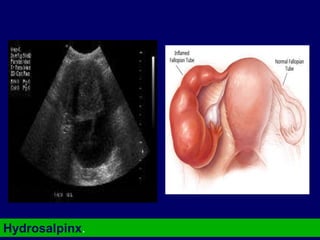

Hydrosalpinx.